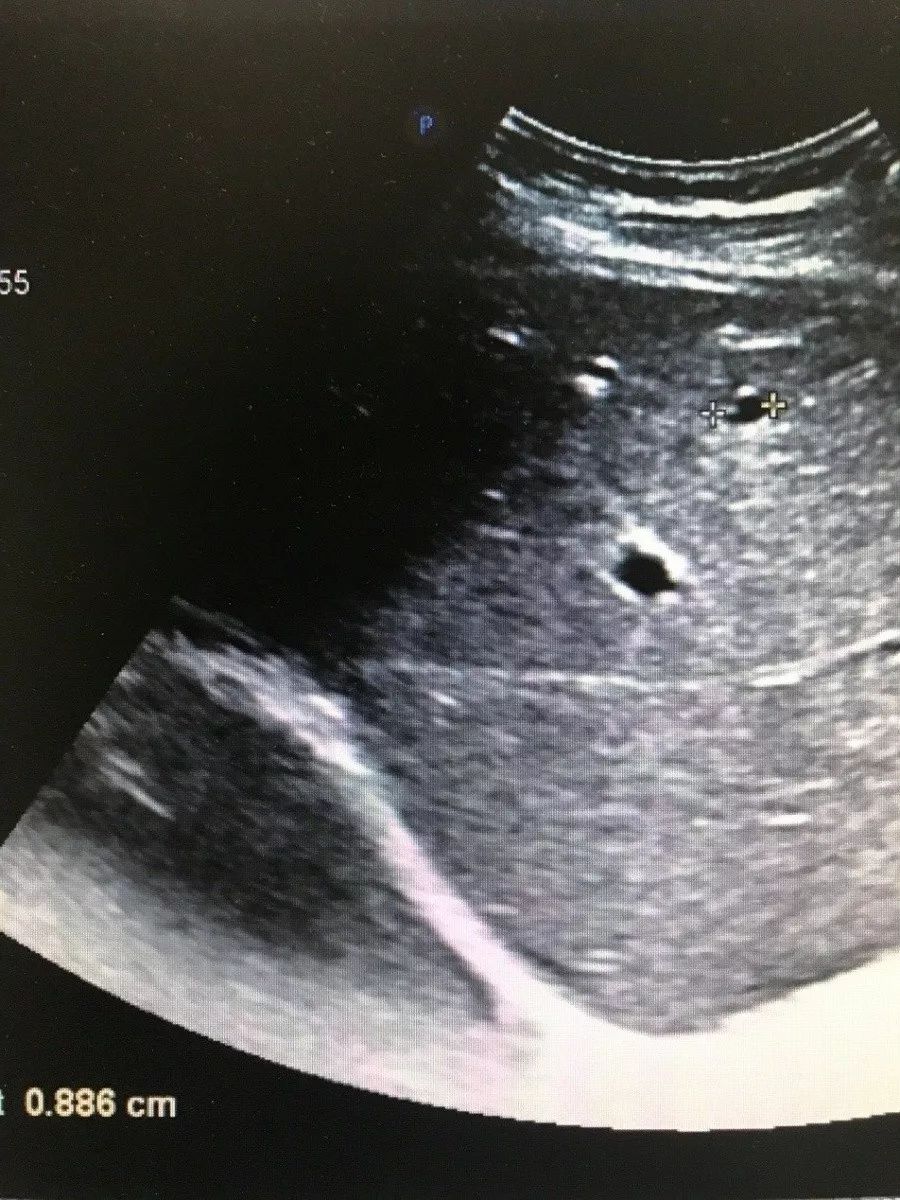

图二

Echo-free interior of liver cyst

These are the contents of today's sharing, I hope it is useful for you. As well as the excellent Ultrasound machines, MCI0580 and MCI0581 available from MeCan, here are their liver images.

图三